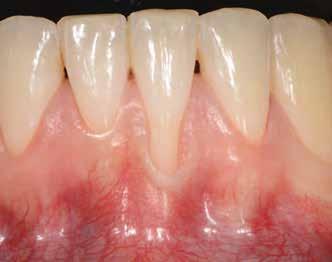

A gyógyulási időszakot követően a csontos gyógyulás ellenőrzése és az implantáció tervezése céljából állcsonti CT-felvételt készítettünk. A CT-felvételen tökéletes csontos gyógyulást észleltünk, az alveoláris csont volumene

Fergeteges

teljes mértékben megtartott, a vertikális augmentáció a tervezettnek megfelelő eredményű volt (13–15. ábra), a klinikai kép is ennek megfelelően alakult, optimális menynyiségű keratinizált ínnyel és azt adekvát sebészi technika eredményeképpen megtartott vesztibulummal (16–17. ábra). Az alsó és felső állcsontba 4-4 darab Bredent COPA Sky implantátumot ültettük, D1-D2 csontminőség mellett,

35 Ncm primer stabilitást mértünk. Nyílt gyógyulási protokollt alkalmazva az ínyformázókat is behelyeztük, amelyek körül az ínyt csomós öltésekkel zártuk (18–20. ábra) Amennyiben lehetséges, mindig nyílt gyógyulási protokollt választunk, így biztosítva elegendő időt a lágyrészek maturációjához (29). Kiemelendő, hogy az irodalmi adatoknak (30, 31, 32) és saját tapasztalatunknak megfelelően az íny biotípusának jelentős, pozitív irányú változását észleltük. Az implantátumokra 180 nap gyógyulási időszakot követően (minden implantátum stabilitása Periotesttel –8-as értékű volt) hagyományos lenyomatvételi módszer és egyéni értékű artikulátor használatával a fogtechnikus (D1 Dental Kft., Garamvári Csaba) overdenture típusú fogpótlást készített (21. ábra)

A protetikai rehabilitációt követően 9 hónappal az alveoláris struktúrák stabilak, a röntgenfelvételen a csontállomány megtartott, a beteg panaszmentes, rágó funkciója kifogástalan, az esztétikai eredménnyel teljes mértékben elégedett (22–23. ábra)